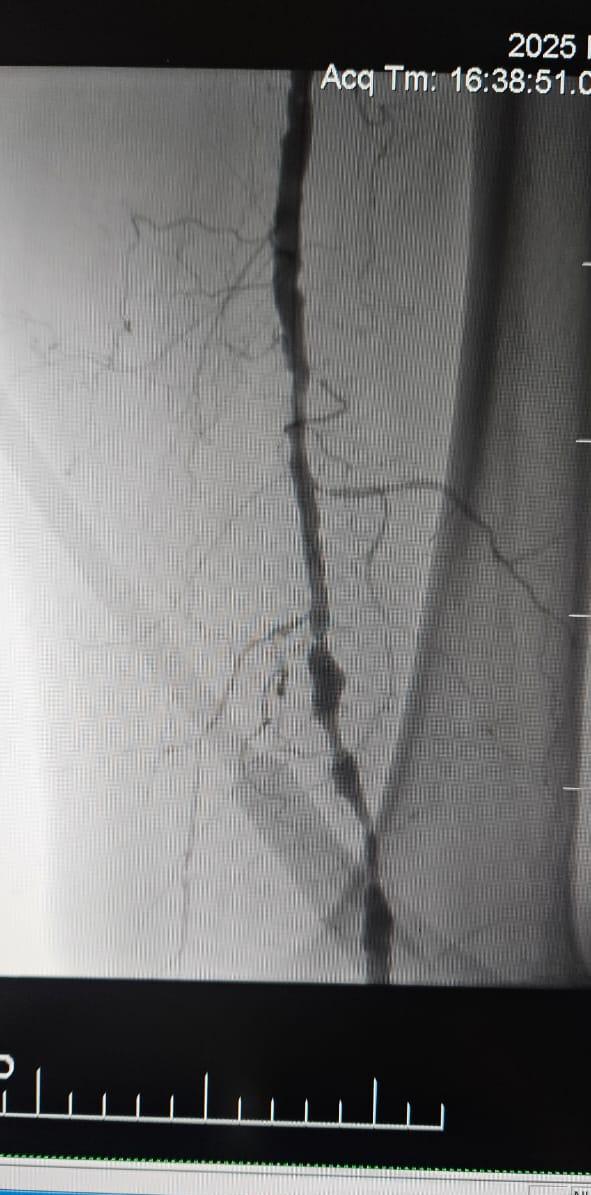

Nos complace compartir un caso exitoso de un hospital en Batumi, Georgia, donde un paciente femenino de 78 años con Isquemia Crítica de Extremidades (CLI) causada por oclusión total crónica de la arteria del miembro inferior mostró una mejoría clínica notable después del tratamiento con el sistema periférico de catéter de dilatación con balón IVL de ThorCrack.

Este caso subraya el valor clínico de la litrotripsia intravascular (IVL) en el tratamiento de casos complejos de CLI con oclusión crónica de segmento largo, particularmente en pacientes con calcificación pesada, donde los balones tradicionales o los dispositivos de aterectomía pueden tener una eficacia limitada.